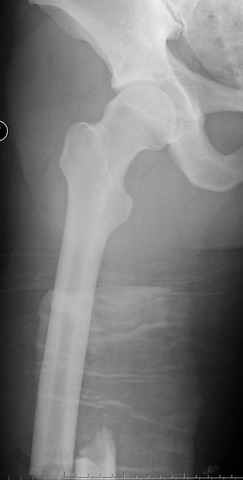

03.14.2005

больному 42, автоавария, политравма, открытая черепномозговая травма, безсознании, открытый перелом бедра, размозжение мягких тканей, дефект кожи на передней поверхности бедра около 13 см2 от ожога, компартмент синдром.

По поводу открытого перелома больной ургентно взят на ретроградное интрамедулярное штифтование, после рутинного дебрайдмента и фасциотомии на бедре и на голени.

перелом бедра

постоперационные

-Согласен, рана до прихода пластического хирурга была 38х13 см, можно было постараться закрыть сверху, а в нижнем отделе где был ожог, применить кожную пластику меньшим размером. К моему удивлению и разочарованию, когда вернулся из другой операционной (шли пареллельные операции), он уже успешно заканчивал свое дело. Кстати недавно разговаривал с нейрохирургом, он снял ICP (intracranial prеssure monitor), внутричерепное давление стабилизировалось, ортопеды и хирурги закончили с лечением, теперь длительное неврологическое восстановление.